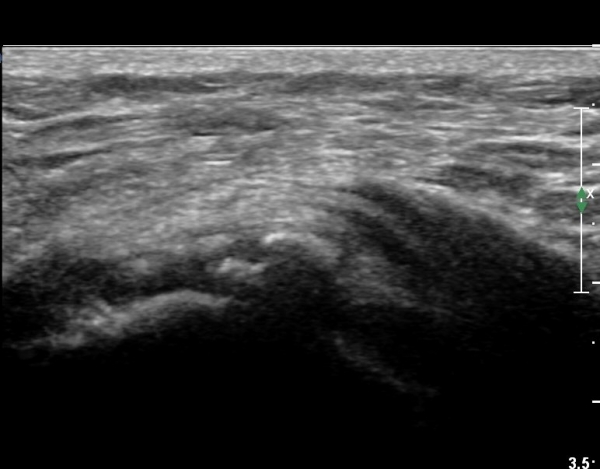

ÃÊÀ½ÆÄ °Ë»ç

Á¡¾×³¶³» ÁÖ»çÄ¡·á¿Í ¼®È¸ÀÇ ÁÖ»ç¹Ù´Ã ÀÚ±Ø(needling)